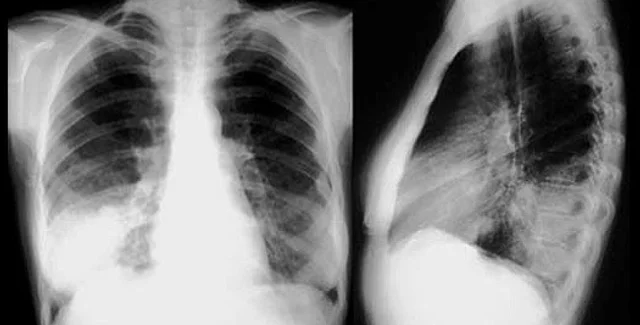

Все жертвы вируса на Буковине (22 человека в возрасте от 20 до 40 лет) умерли не от двусторонней пневмонии, как это считалось ранее, а в результате вирусного дистресс-синдрома, то есть тотального поражения легких

"Во время двусторонней пневмонии отслеживается определенная морфологическая картина. Относительно данных смертей, то здесь такой морфологической картины нет. Вирус, который вызывает смерть, очень агрессивен, он даже не поражает трахею, а сразу попадает в легкие и вызывает сильный их отек и сплошное кровоизлияние. Причиняют такое состояние смешанные типы парагриппа и гриппа А/Н1N1. Это очень токсичный штамм, который до сих пор не поддавался выработанной Минздравом методике лечения", - сказал Бачинский.